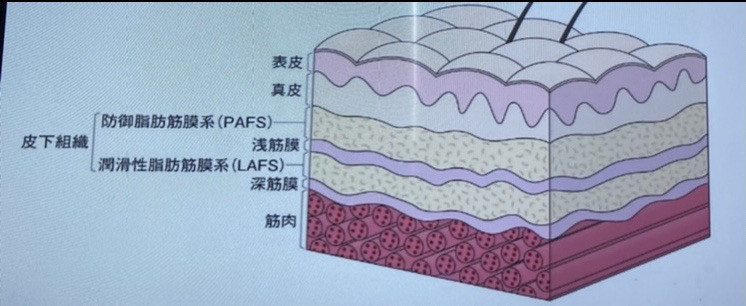

その場だけ治ってもあとでまた痛い場合は仕事や姿勢からくる原因をやっつける必要があります。 筋膜の痛みとは 筋膜リリースについてはいろんな研究がなされています。 その中でもお医者さんが筋肉と筋肉の間にある筋膜を生理食塩水を注射することで大きく痛みの改善ができたことで注目されています。

筋膜のリリースの方法はローラーやストレッチなどいろいろありますが、手技でも改善することができます。 大事なことは浅層の筋膜なのか、深層の筋膜なのかどちらが痛みの原因なのかを理解してアプローチすることが大切です。

浅筋膜は皮膚を動かして緩めることができます。 深筋膜は皮膚をつまんで動かすことによって緩められます。 悪いところの滑走性が改善すると痛みが解消するというわけです。

マッサージでも改善しない場合は筋膜からの痛み、姿勢の改善が必要かもしれません。